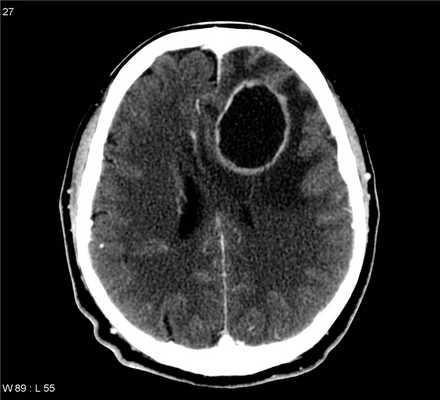

Абсцесс головного мозга и МРТ

Подтвердит или опровергнет диагноз абсцесса головного мозга МРТ-диагностика. Магнитно-резонансная томография показывает изменения в веществе головного мозга на ранней стадии развития воспалительного процесса (церебрите). Данная стадия длится всего 3-5 дней, и за этот промежуток времени капсула абсцесса не успевает сформироваться.

На поздней стадии церебрита (от 5 до 14 дней) на фоне перифокального* отека головного мозга формируется участок некроза (полость, заполненная гноем). В ходе МРТ хорошо виден центральный некроз и сопровождающая его зона отека.

После 14-го дня формируется капсула абсцесса с обширной зоной отека вокруг него. МР-томография хорошо дифференцирует сам абсцесс, его капсулу и сопровождающий перифокальный отек. Чаще всего абсцессы головного мозга приходится дифференцировать с метастазами кистозного типа: основой в дифференциальной МРТ-диагностике этих состояний являются диффузионно-взвешенные изображения.

При МРТ отсутствует ионизирующее излучение, свойственное КТ и рентгенографии, поэтому МР-томография является абсолютно безопасной для здоровья человека процедурой. На этапе контроля лечения абсцесса МРТ может использоваться так часто, как этого требует здоровье пациента.